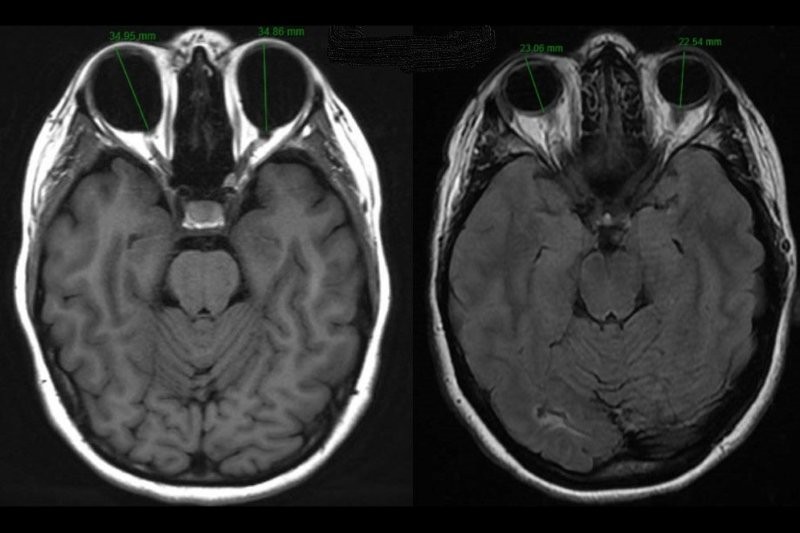

Differentiating papilloedema from pseudopapilloedema in children

Drs Martin Wasik and Helen Kearns

01/08/2025